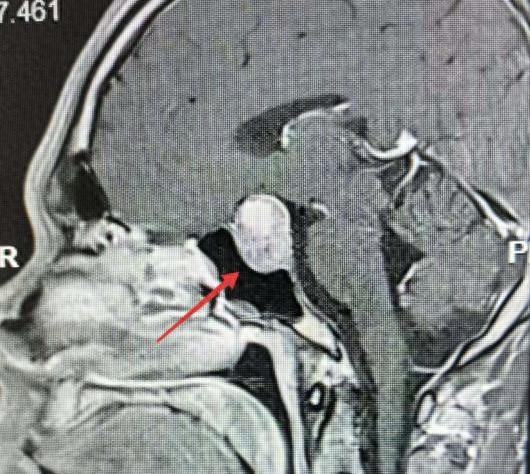

原以为是亚健康的他,在感觉到颈椎不适难以忍受后,来到南通市第一人民医院骨科就诊。可检测报告显示无明显异常。经过进一步检查,最终医生发现李先生大脑深处长出了一枚巨大的生长激素垂体腺瘤。

医生表示李先生已突发垂体瘤急性卒中,瘤体内出现出血坏死,随时可能引|发昏迷休克,几小时内就可能危及生命。